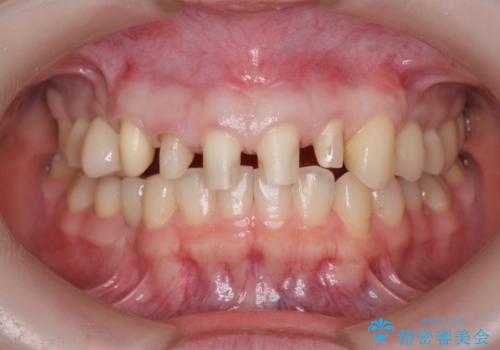

多発した前歯の重度虫歯治療

- 放置した虫歯の歯がボロボロになってしまい治療を希望され来院されました。

残根状態の歯、神経まで虫歯が達し失活した歯、歯肉縁下まで及んだ虫歯が多数認められます。